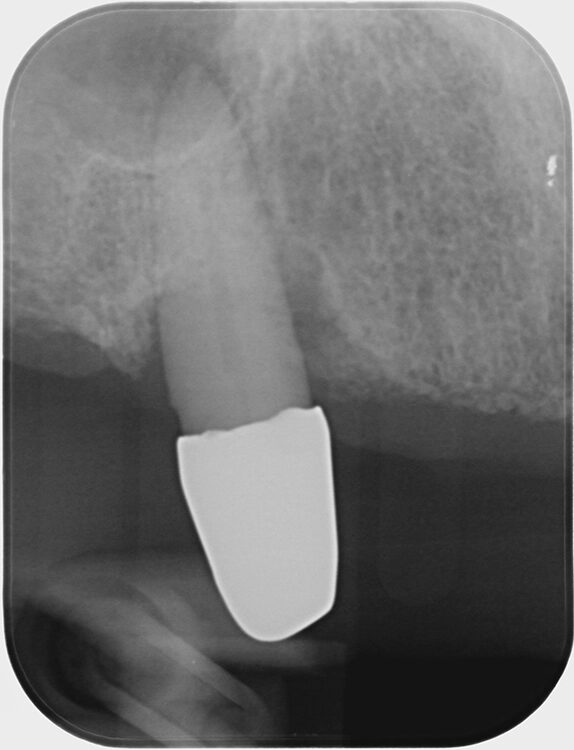

Abb. 6 a–h: Klinische und radiologische Dokumentation 7 Monate nach der AIT und der Applikation von Straumann® Emdogain® an den Zähnen 13 und 23. Die Sondierungstiefen und die parodontal entzündete Wundfläche haben sich im Vergleich zu den initialen Befunden deutlich reduziert. Es lagen keine Sondierungstiefen >5 mm vor. Das bedeutet, es bestand zu diesem Zeitpunkt keine Indikation für ein weiteres ggf. chirurgisches Vorgehen.Walter

Abb. 6 a–h: Klinische und radiologische Dokumentation 7 Monate nach der AIT und der Applikation von Straumann® Emdogain® an den Zähnen 13 und 23. Die Sondierungstiefen und die parodontal entzündete Wundfläche haben sich im Vergleich zu den initialen Befunden deutlich reduziert. Es lagen keine Sondierungstiefen >5 mm vor. Das bedeutet, es bestand zu diesem Zeitpunkt keine Indikation für ein weiteres ggf. chirurgisches Vorgehen.

Die klinische und radiologische Untersuchung nach der AIT und der Applikation von Straumann® Emdogain® an den Zähnen 13 und 23 erfolgte nach 7 Monaten. Die Sondierungstiefen und die parodontal entzündete Wundfläche hatten sich deutlich reduziert (Abb. 6). Es lagen keine Sondierungstiefen >5 mm mehr vor. Auch radiologisch konnten Umbauvorgänge und Kortikalisierungen auf den Einzelbildern im Vergleich zur initialen Panoramaschichtaufnahme festgestellt werden. Somit bestand zu diesem Zeitpunkt keine Indikation für ein weiteres ggf. parodontalchirurgisches Vorgehen.